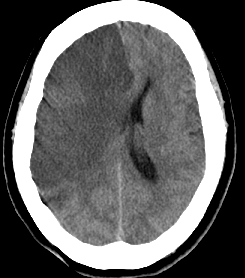

くも膜下出血のCT

【くも膜下出血のCT】

Apoplexy 14

【脳動脈瘤;矢印の部位】